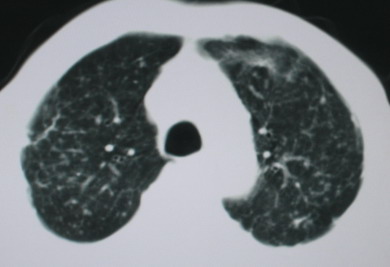

以下是引用卜一在2008-6-3 19:33:00的发言:[br]双肺结节,以双上肺分布为多,期间搀杂片状致密影及索条致密影。考虑:继发性肺结核伴血型播散可能性大。不除外肺泡ca的可能!另:椎体退变!

以下是引用panyishengct在2008-6-3 21:09:00的发言:[br]双上肺弥漫性小结节影,纵隔窗内钙化淋巴结影,考虑矽肺或/和tb可能性较大,不除外肺ca可能。腰椎考虑退变。 [br][br]